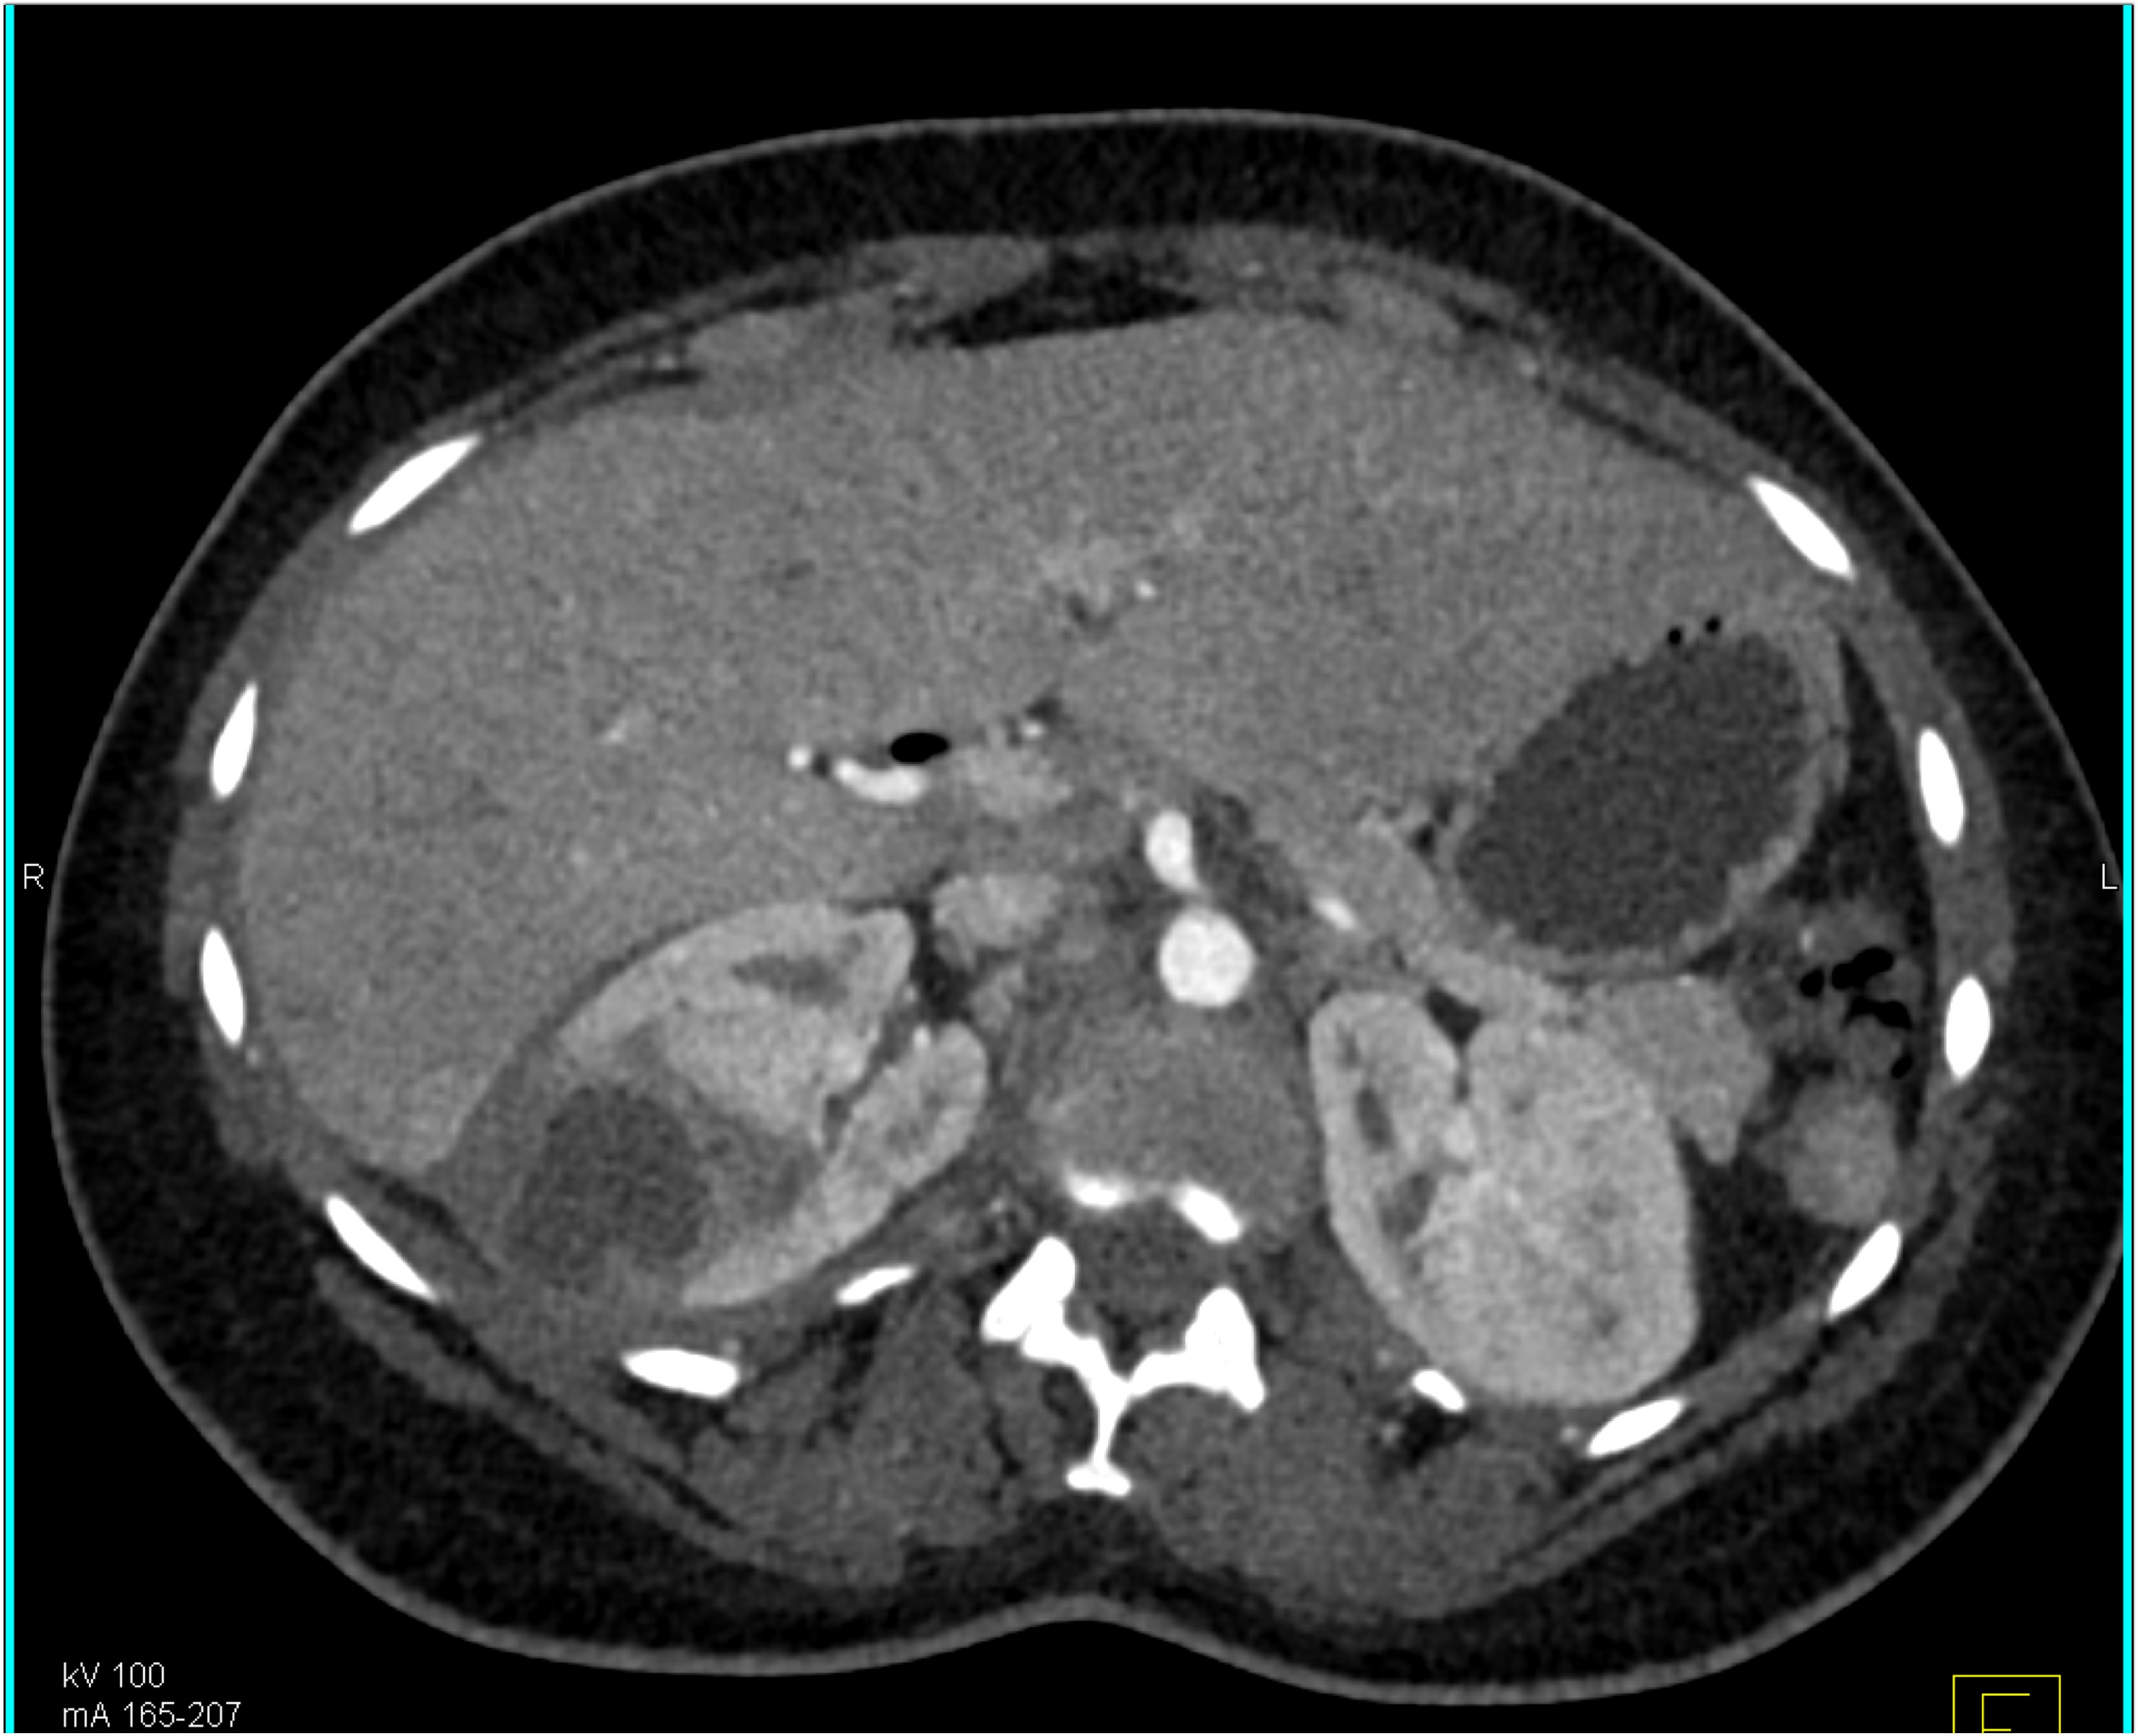

4) In this patient with sickle cell disease the most likely diagnosis is?

lymphoma

renal cell carcinoma

renal abscess

MEST tumor